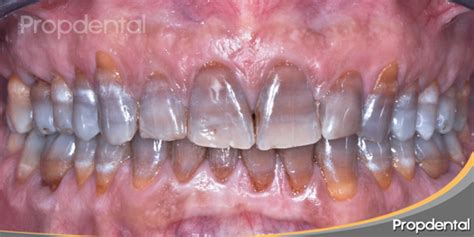

Como son las manchas por tetraciclina: dientes grisáceos en bandas. Las manchas de tetraciclina son discromías o alteraciones del color dentario. Las manchas provocadas por tetraciclina no son simples manchas individuales.

Se distribuyen en patrones de bandas horizontales a lo largo de los dientes, creando un aspecto bastante característico. Estas bandas pueden ser más claras o más oscuras, y su intensidad depende del momento exacto en que se tomó el antibiótico durante el desarrollo dental.

En etapas tempranas, los dientes frontales son los más afectados, mientras que en fases más avanzadas pueden verse comprometidos los molares. La exposición solar también influye, ya que al oxidarse los pigmentos, la tonalidad puede oscurecerse aún más con el tiempo. En algunos casos, el color puede derivar en tonos marrones o incluso negruzcos.

En función de su tonalidad, extensión e intensidad, las manchas en los dientes por tetraciclinas se pueden clasificar en diferentes grados.

Este tipo de manchas se caracterizan por ser leves y de color amarillo o gris claro. En este caso, las manchas dentales por tetraciclinas son más evidentes. En este es el grado más severo de decoloración, por eso, en estos casos, los dientes pueden tener una apariencia prácticamente negra.

Como ya hemos mencionado, el grado de tinción de los dientes debido a la tetraciclina depende, especialmente, de la cantidad de medicamento suministrado y de la duración del tratamiento. En el tercer grado, las manchas toman un tono más oscuro de gris o tornan a un tono azulado.

Cuarto grado: son las tinciones más graves, de color más fuerte y que afectan a todo el diente. En función del grado de coloración se establecen cuatro categorías. Desde una leve variación cromática, que por lo general tiende a un color gris, hasta el nivel más extremo y poco común, que produce alteraciones en la textura dental y rallas horizontales que varían en cromatismo.